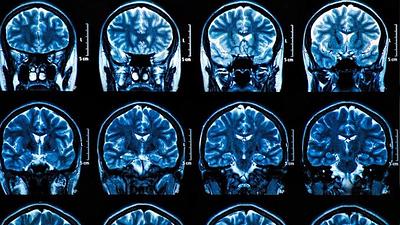

Exame de sangue pode detectar Alzheimer antes de primeiros sintomas

Desenvolvido por pesquisadores alemães e americanos, teste identifica no sangue proteína gerada na morte das células nervosas, até 16 anos antes do aparecimento da doença.